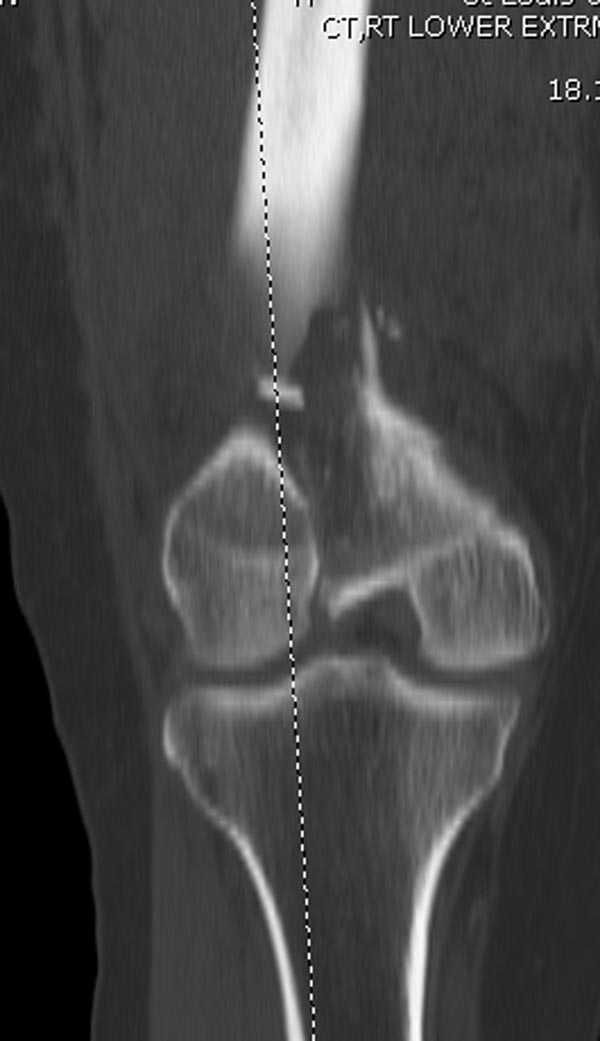

Бесспорно, предлагаемый ретроградный метод имеет свои преимущества, но имеется опасность при манипуляции интрамедуллярным гвоздем расколоть мыщелки.

Раскол можно предупредить шурупами, но короткий дистальный фрагмент навряд ли позволит добиться адекватной стабильности конструкции. Стандартные гвозди не рассчитаны для таких переломов, и если все таки желаете провести фиксацию гвоздем, тогда надо заказывать специальный custom made nail т.е. с расширенной возможностью дистальной блокировки.

Поэтому такие меж и над- мыщелковые переломы более предпочтительным считается фиксировать мыщелковыми пластинами

Устанавливается из малого разреза "не вскрывая сустав" со стороны латерального мыщелка, и Insertion Jig позволяет установить пластину "мостовидно" перкутанно в проксимальном отделе, "не вскрывая и не трогая" место перелома.